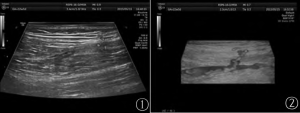

近年來發表學術 5篇,承擔省市級科技攻關課題《超聲三維造影在穿支皮瓣血管術前定位中的套用》

超聲三維造影